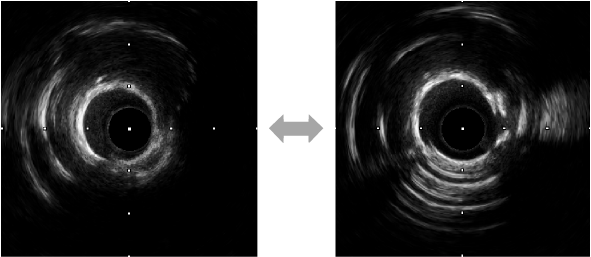

前后IVUS对比

再次IVUS评估

IVUS结果:可见近段及中段多处钙化环断裂,管腔狭窄明显改善;远端钙化环较厚未见明显断裂,管腔扩张不充分。

用2.5mm高压球囊对远端病变进行充分扩张后,行IVUS可见明显钙化环断裂。

IVUS结果:远端钙化处可见360°钙化环断裂,多重反射影;远端血管直径约2.5mm。